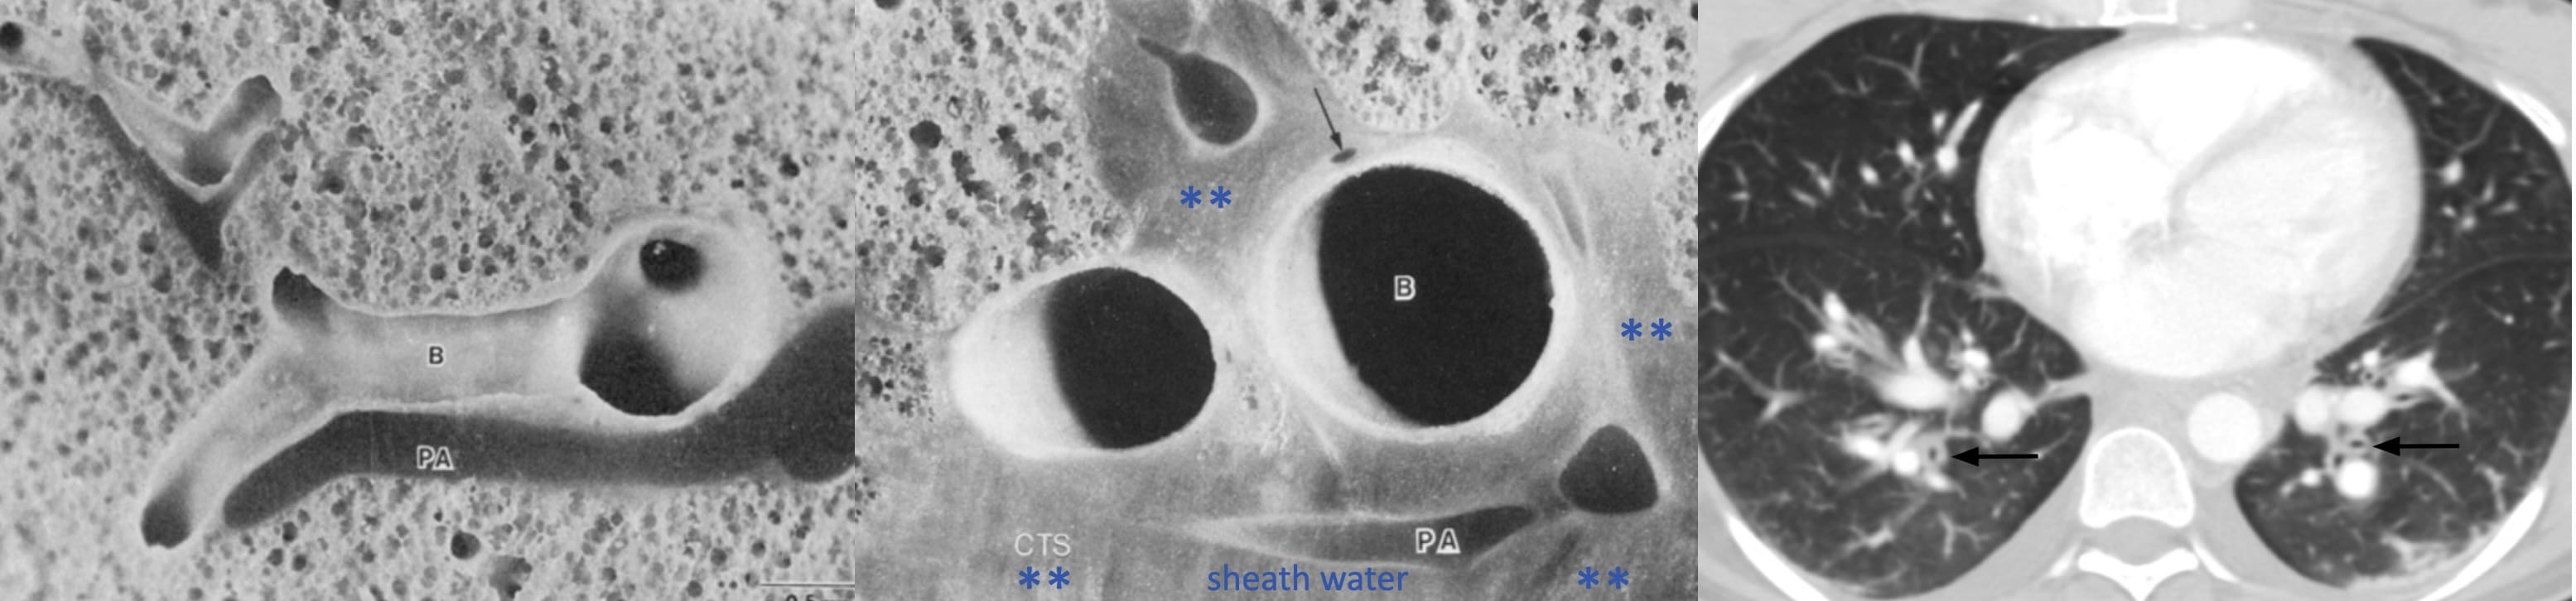

Peri-bronchial fluid cuff

The broncho-arterial bundle—bronchi and arteries run together—is surrounded by a connective tissue sheath This is shown in this animal model-derived micrograph, before and after it is filled with water (***), with a corresponding CT image alongside.

Signs of Interstitial Edema

When two of these sub-visceral pleural compartments are contiguous, as is the case in relation to the interlobar fissures, the accumulating fluid (blue asterisks) suggests “thickening” of the fissures.